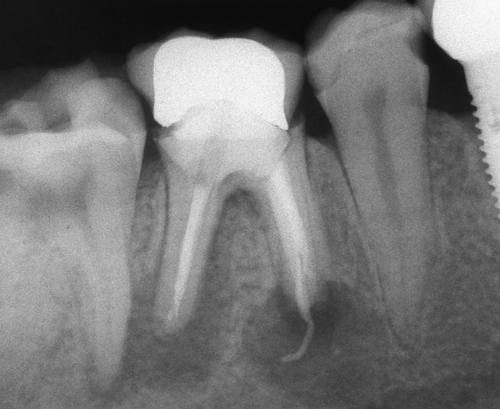

Оралната хирургия е дял от денталната медицина. Понятието орална хирургия е доста условно - с него се обозначават различни видове оперативни интервенции в областта на устната кухина, въпреки че дори и почистването на един кариес по своята същност представлява оперативна интервенция (некректомия); екстирпацията на един нерв от зъбен канал, почистването на зъбен камък, пиленето на зъб за корона и запълването на коренов канал също са оперативни интервенции, понякога технически доста сложни. Все пак всички тези манипулации са извън обема на оралната хирургия - тя включва екстракцията на ретинирани зъби, отстраняването на кисти от зъбен произход, на малки по обем доброкачествени тумори, и, разбира се, поставянето на зъбни импланти. Всички необходими манипулации за осъществяването на костна пластика при имплантатите също влизат в обема на оралната хирургия.